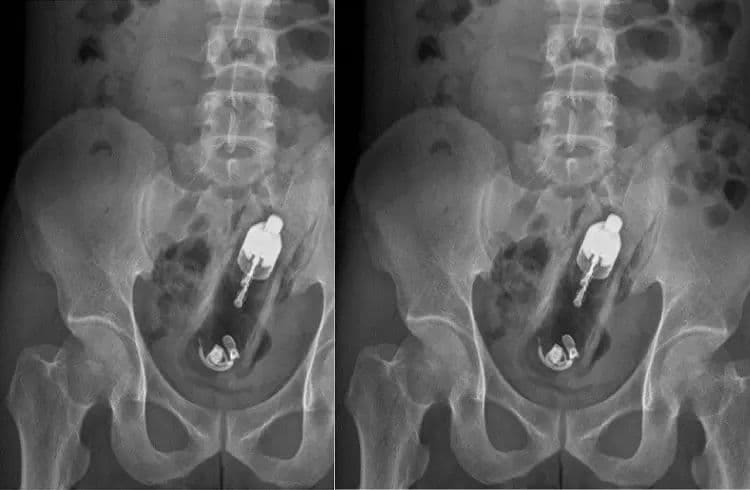

ತೈವಾನ್ನ ಕಾವೋಸಿಯುಂಗ್ನ 24 ವರ್ಷದ ಯುವಕನೊಬ್ಬ ತೀವ್ರ ಹೊಟ್ಟೆ ನೋವಿನಿಂದ ಆಸ್ಪತ್ರೆಗೆ ದಾಖಲಾಗಿದ್ದ. ಈ ವೇಳೆ ಎಕ್ಸರೇ ಮಾಡಿದ ವೈದ್ಯರು ಅವರ ಗುದನಾಳದಲ್ಲಿ 20 ಸೆಂ.ಮೀ ಆಳದಲ್ಲಿ ವೈಬ್ರೇಟರ್ ಸಿಲುಕಿಕೊಂಡಿರುವುದನ್ನು ಕಂಡು ಘಾತಕ್ಕೊಳಗಾಗಿದ್ದಾರೆ.

ವೈದ್ಯರು ಎಕ್ಸ್-ರೇನಲ್ಲಿ ಅದು ಗುದದ್ವಾರದಿಂದ ಕೊಲೊನ್ ವರೆಗೆ ಆಳವಾಗಿ ಸಿಲುಕಿಕೊಂಡಿರುವುದನ್ನು ಕಂಡುಹಿಡಿದರು. ಬಳಿಕ ಅವರು ತುರ್ತು ಶಸ್ತ್ರಚಿಕಿತ್ಸೆಗೆ ಒಳಗಾಗಬೇಕಾಯಿತು, ಆದರೆ ಆಸ್ಪತ್ರೆಯಲ್ಲಿ ವೈದ್ಯಕೀಯ ಸಿಬ್ಬಂದಿ ಕೊರತೆಯಿಂದಾಗಿ, ಎರಡು ದಿನಗಳ ನಂತರ ಅವರಿಗೆ ಶಸ್ತ್ರಚಿಕಿತ್ಸೆ ಮಾಡಲಾಯಿತು. ಆದಾಗ್ಯೂ, ಸುಮಾರು ಎರಡು ಗಂಟೆಗಳ ಕಾಲ ನಡೆದ ಶಸ್ತ್ರಚಿಕಿತ್ಸೆಯ ನಂತರ, ವೈದ್ಯರು ಅವರ ದೇಹದಿಂದ ವೈಬ್ರೇಟರ್ ಅನ್ನು ಹೊರತೆಗೆದರು. ವೈಬ್ರೇಟರ್ ಹೊರತೆಗೆದಾಗಲೂ ಅದು ಆನ್ ಆಗಿತ್ತು ಎಂಬುದು ಗಮನಾರ್ಹ.